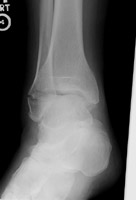

- Click on the image for a larger versionBMortise radiograph of the ankle. The fracture is difficult to visualize.

Weber A fractures consist of fibular fractures distal to the level of the tibiotalar joint. These fractures are generally treated nonoperatively. The syndesmosis between the tibia and fibula remains intact. The fracture results from supination-adduction injuries. The medial malleolus may be fractured or the deltoid ligament may be disrupted.